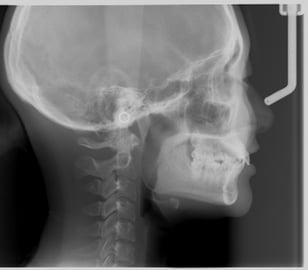

今まで歯科のレントゲン診断は全て平面で情報が得られないため、本来ある病変がレントゲン像では重なって覆い隠されてしまったり、立体的な位置関係がわからないため、限られた情報しか得られませんでした。

歯科用CTの導入により高解像度で立体像が得られるため、今までにない診断が得られるだけでなく、インプラント・矯正治療・精密根管治療・口腔外科手術なども今まで以上に安全に行えるようになりました。

同じCTでも腹部CTなどと違い低被ばくで安心です。

ひずみの少ない像で顎全体が写るパノラマレントゲンのみならず、顎関節撮影、矯正治療で必要なセファロレントゲンも撮影できます。